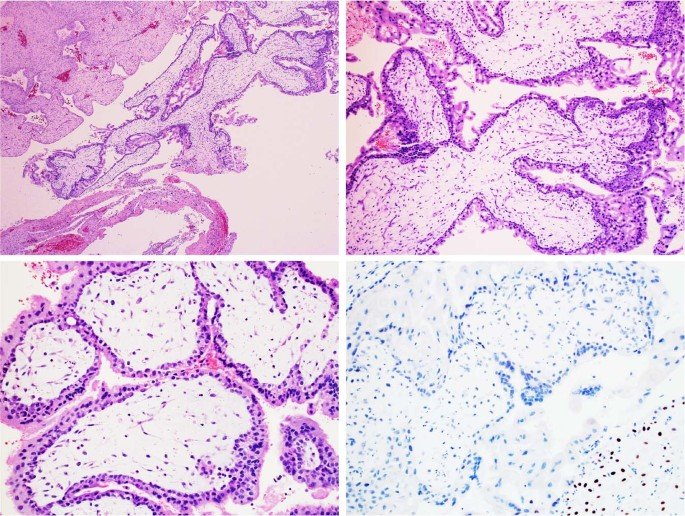

what is Choriocarcinoma/gestational trophoblastic neoplasia?

Gestational trophoblastic disease (GTD) is the term given to a group of rare tumors that develop during the early stages of pregnancy. After conception, a woman’s body prepares for pregnancy by surrounding the newly fertilized egg or embryo with a layer of cells called the trophoblast. The trophoblast helps the embryo implant itself to the uterine wall. These cells also form a large part of the tissue that make up the placenta — the organ that supplies nutrients to a developing fetus. In GTD, there are abnormal changes in the trophoblast cells that cause tumors to develop.

Choriocarcinoma: This cancerous tumor forms inside a pregnant woman’s uterus. Choriocarcinomas usually occur when growths from molar pregnancies turn cancerous. Rarely, choriocarcinomas form from tissue left in the uterus after a miscarriage, an abortion or the delivery of a healthy baby.